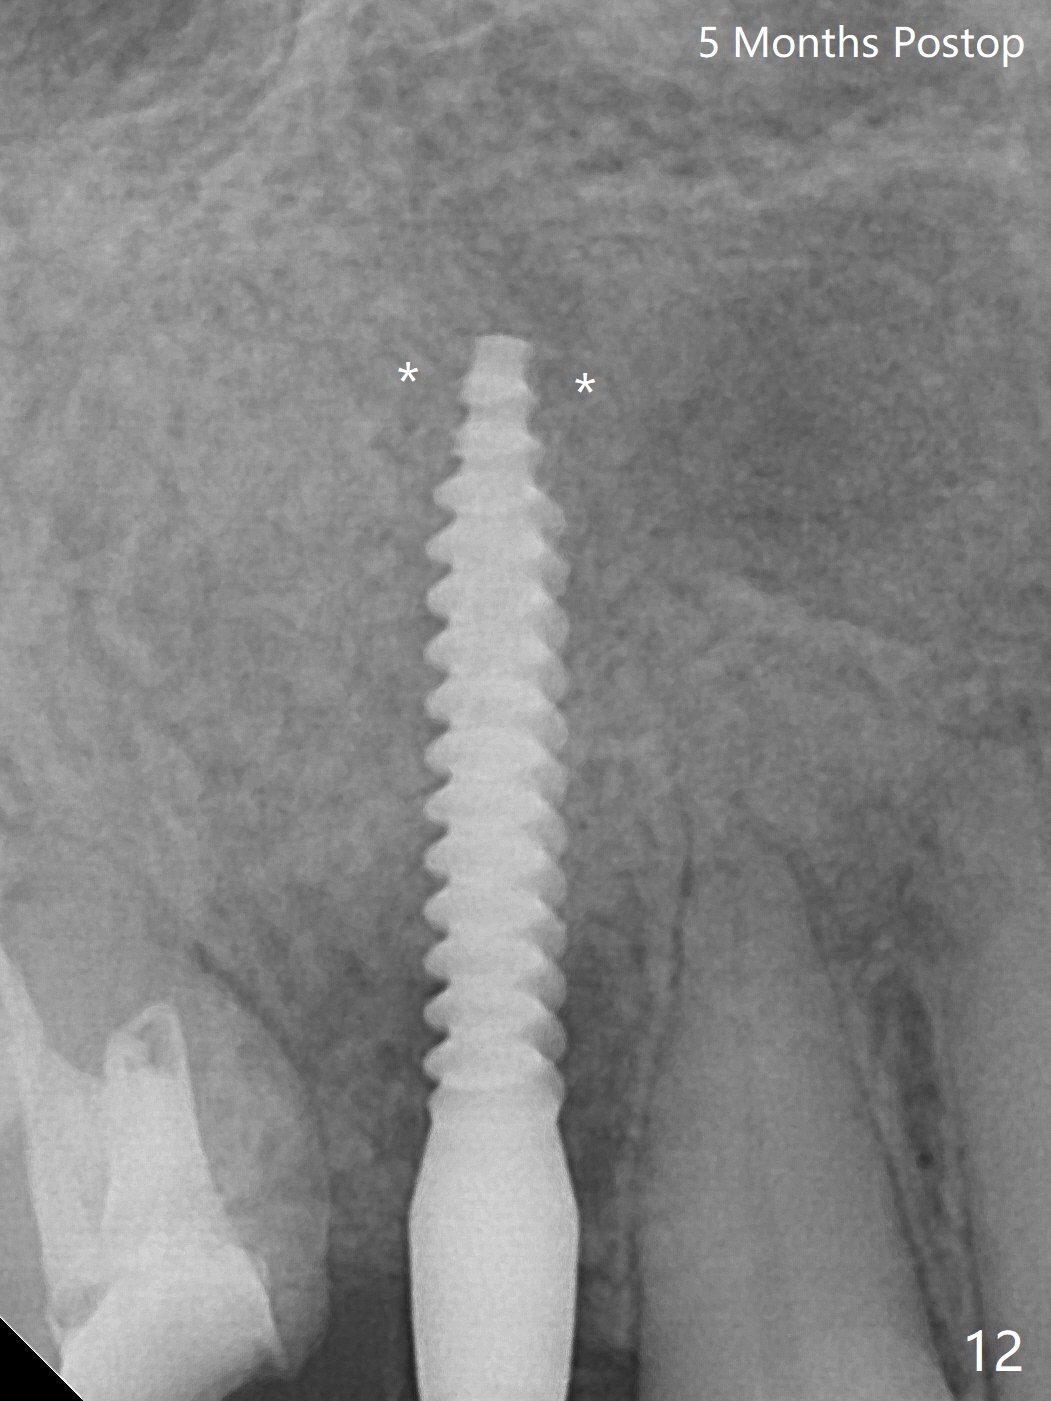

Osteotomy starts with guide and 2.2 mm drill for initial 3.5 mm palatal. A semilunar incision is made buccal to remove the impacted canine (#6 by sectioning). With direct vision buccal and palatal, the final osteotomy is finished free hand with 1.2 and 1.5 mm drills. Initially buccal perforation occurs, the osteotomy route is corrected later (Fig.1). When a 2.5x15 mm 1-piece implant is being placed, it perforates into the buccal concavity again. After redirection, the trajectory seems to be acceptable (Fig.2: CT coronal section). Three coronal implant threads are exposed partially palatal (Fig.3: CT 3-D palatal view). The implant is then turned 2-3 times with insertion torque reaching 40 Ncm. The incision is closed with suture following Osteogen plug placed in the most coronal portion of the socket (Fig.4 P) and allograft (*) in the remaining socket around the apical portion of the implant as well as palatal. The incision does not heal 1 month postop (Fig.5). PRF membrane will be placed next visit. Next visit the wound in fact is healing (Fig.6). PRF is unnecessary. The patient will return for impression 3 months postop. To be cosmetically pleasing, prepare local anesthetic and Laser for gingivectomy (Fig.7 red curved line). There is no bone loss around the implant 3.5 months postop (Fig.8). With topical, minor gingivectomy with laser creates papillae mesial and distal to the implant (Fig.9, 10 (incisal view)). After reline, there is appearance of a canine (Fig.11). The patient returns for impression 5 months postop; there is bone around the apex of the implant (Fig.12 *). The hard and soft tissues remain healthy when final restoration is delivered (Fig.13,14). The buccal plate reforms and #6 socket heals 12 months postop (6 months post cementation, Fig.15). The gingiva remains healthy at #4-6 nearly 2 years post cementation (Fig.16).